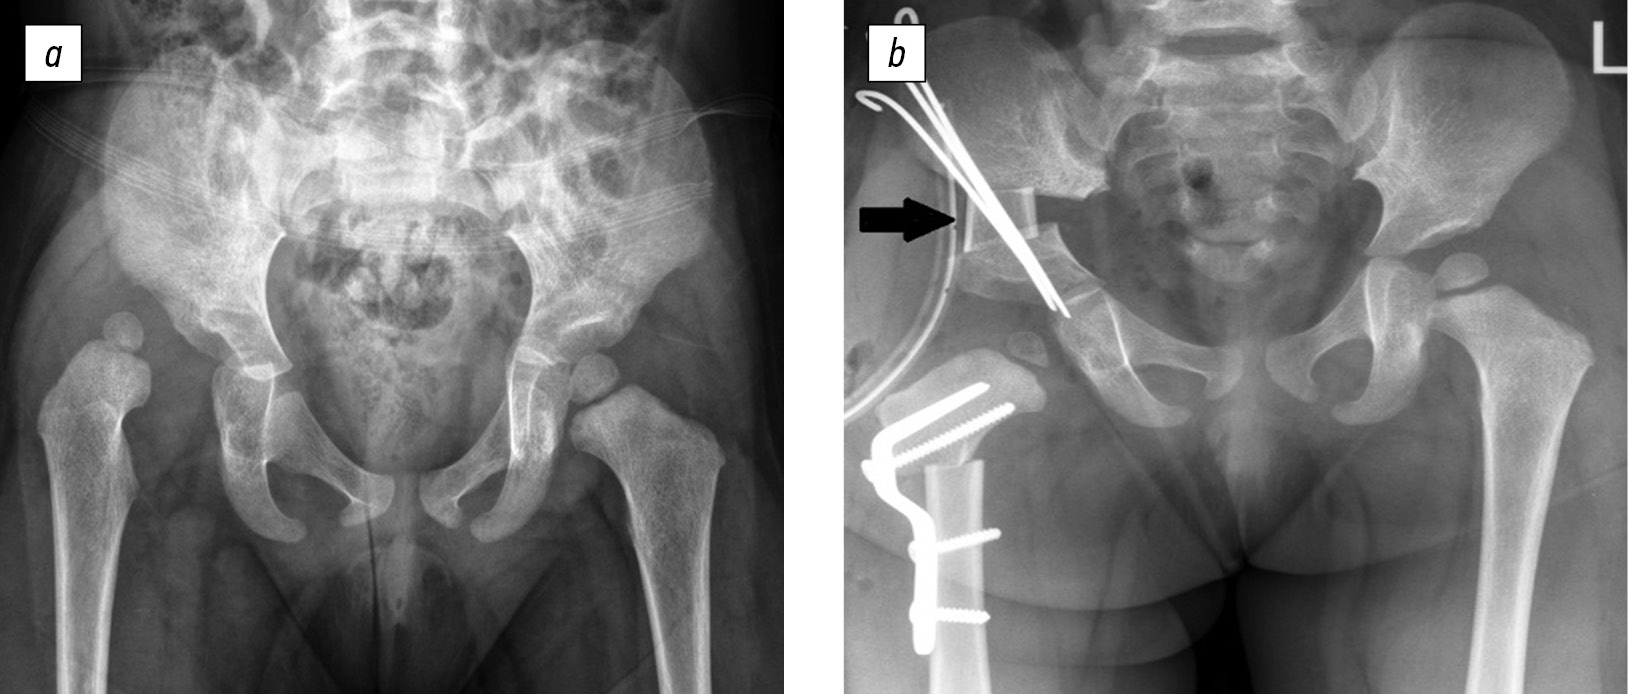

For adequate comparative analysis, similar indicators of the contralateral (“healthy”) joint were analyzed using archived radiographs of 50 patients (50 hip joints) with Tönnis grade II–IV hip dysplasia, who underwent the modified Salter surgery, which was traditionally performed in the Department of the Hip Joint Pathology of the H.I. Turner National Medical Research Center for Children’s Orthopedics and Trauma Surgery, without verification of the type of acetabular deformity, using an autograft from the femur, which was placed in the diastasis of the iliac fragments (Fig. 3).

Fig. 3. Radiograph of patient Z., 3 years old, with Tönnis grade III dysplasia of the right hip joint: a, before surgery; b, after radical reconstruction with a modified Salter surgery using an autograft from the femur (indicated by an arrow)